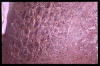

Eritema ab igne